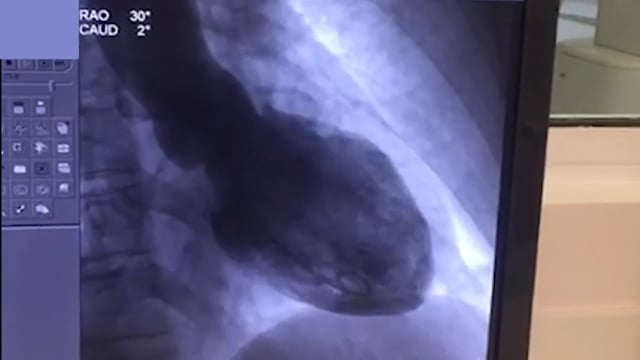

Vídeo 1

Ventriculografia

A paciente foi levada para a sala de hemodinâmica. A angiografia não identificou obstruções significativas nas artérias coronárias. A ventriculografia está no video 1.

O achado de disfunção grave do ventrículo esquerdo com hipocinesia/acinesia apical e coronárias sem lesões obstrutivas é o quadro típico da síndrome de Takotsubo, também chamada de cardiomiopatia induzida por estresse (https://pubmed.ncbi.nlm.nih.gov/28606950/).

As alterações de motilidade do ventrículo esquerdo (VE) na cardiomiopatia por estresse podem se apresentar de 5 formas:

• Acometimento apical com o achado de balonamento apical do VE (80% dos casos)

• Acometimento da região média do ventrículo com preservação do ápice (segundo tipo mais comum)

• Hipocinesia basal com a região média e apical normais (Takotsubo reverso)

• Tipo focal - um segmento isoladamente comprometido

• Global - hipocinesia global

Na maior parte dos casos, a alteração da motilidade da parede se estende além do território de uma única coronária.